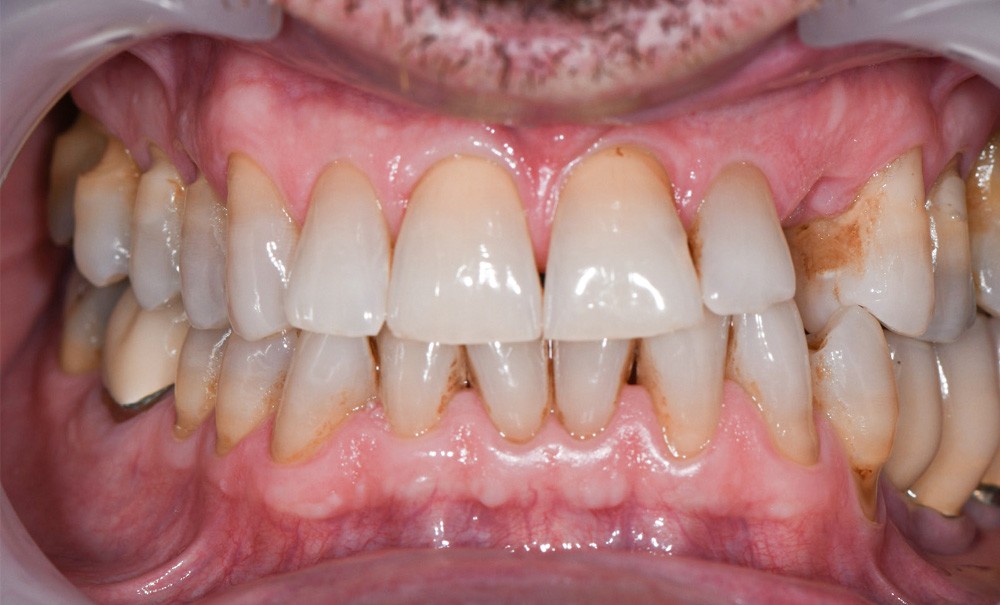

Ce rapport de cas pose la question des possibilités et des limites des bridges collés cantilevers postérieurs en céramique sur un patient présentant un double édentement (23 et 26) avec une contre-indication à l’implantologie. Le principal enseignement de ce cas est qu’il est possible, malgré des facteurs défavorables sur le plan parodontal, de remplacer 2 dents aussi stratégiques que la canine et la première molaire au sein du même quadrant avec des simples collages. Le résultat obtenu, après 3 ans et demi de recul, répond aux impératifs biologique, fonctionnel, mécanique et esthétique.

Un patient de 54 ans, est adressé par son dentiste en raison de la perte récente de 63 avec une 23 incluse. Il recherche une alternative à l’implantologie en raison d’une contre-indication liée à sa prothèse valvulaire [9]. Bien que cette contre-indication médicale ne soit plus absolue [10], l’inclusion de la canine permanente renforce la contre-indication clinique.